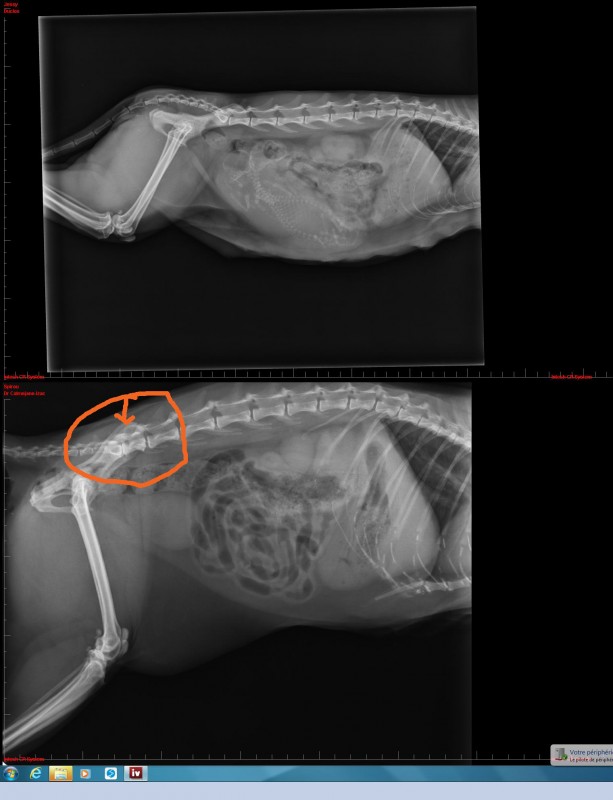

de 24 ans et il y a aussi Monsieur Galou 29 ans qui leurs tient compagnie et fait quelques sorties en longe également. En septembre 2020, Julie et Luna ont été diagnostiquées cushing. Elles sont sous traitement toutes les deux.

pour qu'elle ne se coince pas, ou du moins pas trop régulièrement. Deux fois en deux jours ... c'est